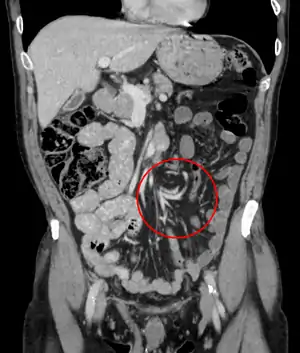

|  | |

| Coronal CT of the abdomen, demonstrating a volvulus as indicated by twisting of the bowel stock | |